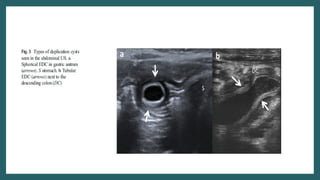

Ultrasound

• Typical gut signature sign present

• Wall is 2-3 mm thick

• Y sign(EDC share wall with adjacent GIT.

Caused by splitting of shared muscularis

propria between cyst and adjacent loop)

• Peristalsis present